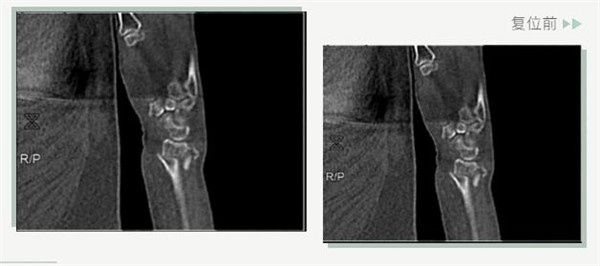

復(fù)位前

25日當(dāng)天,莊阿婆來(lái)到危立軍副院長(zhǎng)門(mén)診,經(jīng)拍片顯示,莊阿婆左橈骨遠(yuǎn)端粉碎性骨折,左髂骨至髖臼后緣及恥骨下支骨折??紤]到莊阿婆年紀(jì)較大,基礎(chǔ)病較多,難以經(jīng)受手術(shù)創(chuàng)傷,傳統(tǒng)手法復(fù)位更為合適。推、拽、按、捺……經(jīng)過(guò)危立軍副院長(zhǎng)一番手法復(fù)位后,再次拍片顯示莊阿婆橈骨遠(yuǎn)端骨折端復(fù)位位置良好,莊阿婆及其家人感到非常滿意。

復(fù)位后